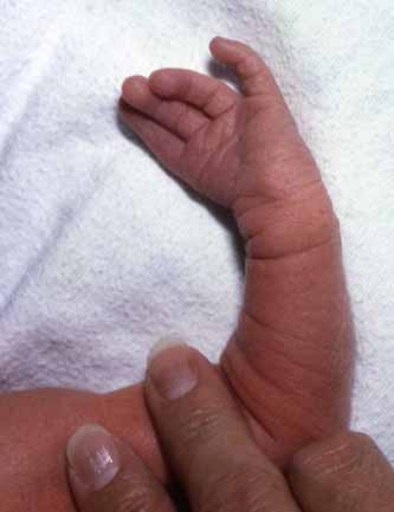

در اين ناهنجاري که چندان کمياب نيست يک انگشت و بندرت دو انگشت اضافي در قسمت بيروني پا به صورت زائـدهاي وجـود دارد که بايد از نظر زيبايي و راحتي در کفش پوشيدن ٬ به وسـيله عمل جراحي برداشته شود . پلی داکتیلی به معنای داشتن انگشت اضافی یا انگشتان اضافه در دست یکی از شایعترین ناهنجاری های مادرزادی دست است و از هر 500 تولد در یک نفر وجود دارد و میتواند به اشکال متعددی ظاهر شود:

- یک برجستگی کوچک در کنار دست

- یک انگشت که در انتها پهن شده و دو ناخن دارد

- یک انگشت اضافه که با یک پایه نازک از کنار دست آویزان است

- یک دست با ظاهر معمولی با یک شست و پنج انگشت دیگر

- و بسیاری اشکال دیگر

پلی داکتیلی یا چند انگشتی میتواند به شکل های گوناگونی ایجاد شود. گاهی پلی داکتیلی همراه با سین داکتیلی یا به هم چسبیدن انگشتان است .از لحاظ مکانی انگشت اضافه بیشتر در طرف انگشت کوچک دست است ولی میتواند در طرف انگشت شست هم باشد. بندرت انگشت اضافه در بین انگشتان وسطی قرار گرفته است . انگشت اضافه ممکن است فقط یک پوست اضافه باشد. ممکن است استخوان هم داشته باشد. ممکن است یک بند و یا چند بند استخوانی داشته باشد و یا حتی ممکن است استخوان آن با استخوان های کف دست مفصل شود. گاهی اوقات هم یک انگشت در انتها دو شاخه شده و یه دو انگشت تبدیل میشود .